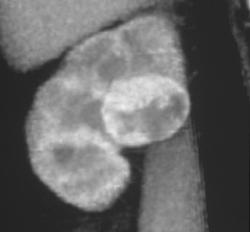

End Stage Kidney Disease (chronic Pyelonephritis)